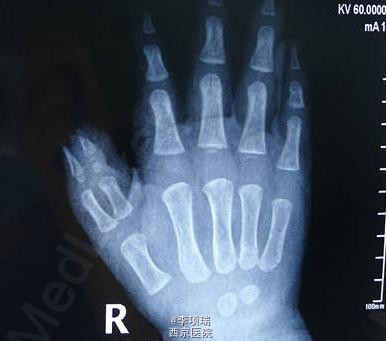

患儿,男,1岁,四型多指,两个指头均细小,切除一个的话拇指太细小,融合的话,两个指头又不等长。故设计切除桡侧指,保留桡侧指半侧软组织及指甲,与尺侧指融合。因为桡侧指短,于指根部做v-y推进,使两个组织块等长。